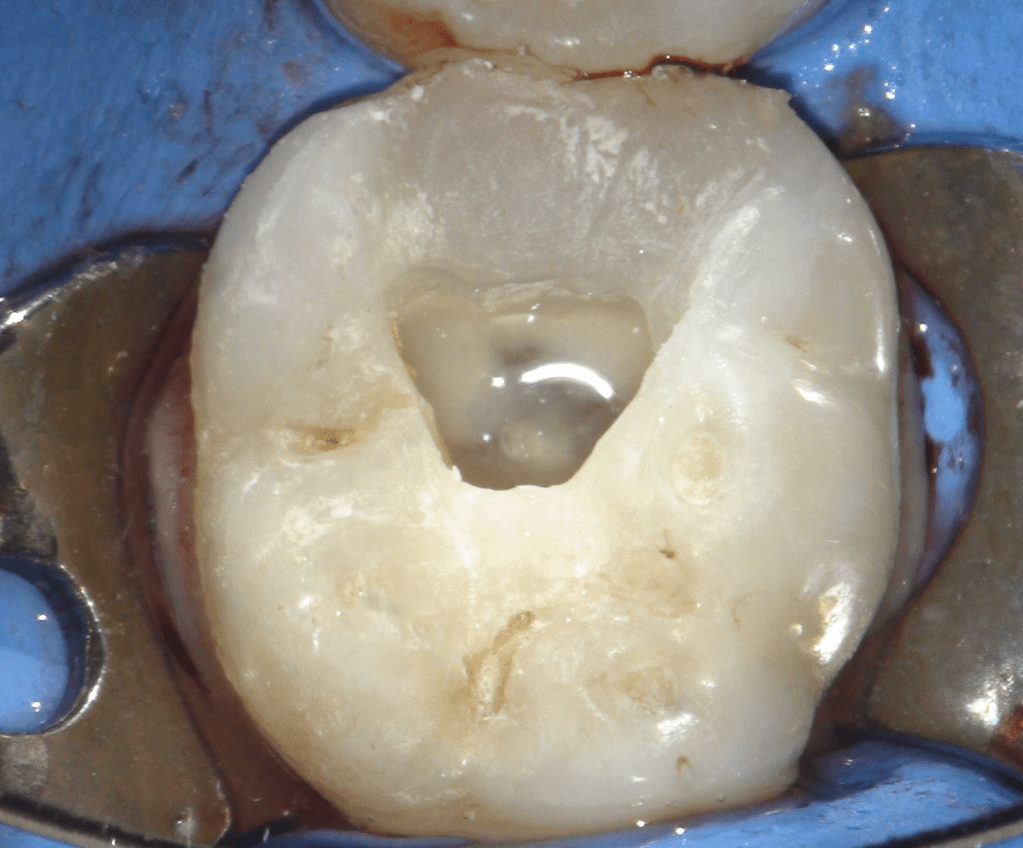

Reconstrucción preendodóntica

Reco preendo + 4 conductos molar superior